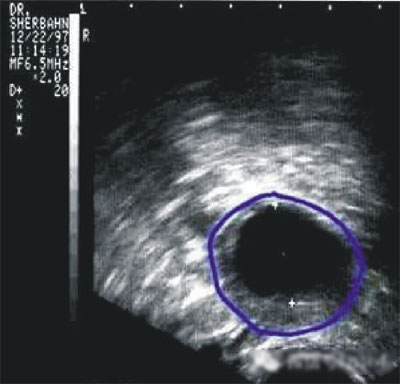

陰道B型超聲動態(tài)監(jiān)測卵泡的發(fā)育及排卵,是監(jiān)測排卵最準(zhǔn)確可靠的方法。通過陰道B超檢查可以了解子宮及雙側(cè)附件(卵巢和輸卵管)區(qū)的基本情況,測定卵巢內(nèi)的竇卵泡計(jì)數(shù),評估卵巢儲備功能,動態(tài)監(jiān)測排卵。